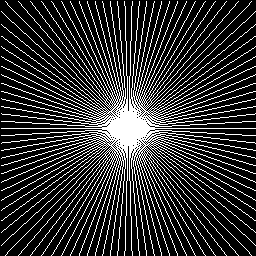

Refer to caption

(a) 10%

(b) 20%

(c) 30%

(d) 40%

Figure 7: Radial sampling masks used in our experiments.

We used two sets of MR images from the IXI database444\urlhttp://brain-development.org/ixi-dataset/ (the brain dataset) and from the Data Science Bowl challenge 555\urlhttps://www.kaggle.com/c/second-annual-data-science-bowl/data (the chest dataset) to assess the performance of our method by comparing our results with state-of-the-art CS-MRI methods (e.g., Convolutional sparse coding-based [20, 21], patch-based dictionary [19, 37, 18], deep learning-based [26, 24, 25, 27], and GAN-based [33, 32]). The image resolution of each image is 256x256. From each database, we randomly selected 100 images for training the network and another 100 images for testing (validating) the result. We conducted the experiments for various sampling rates (i.e., 10%, 20%, 30%, and 40% of the original k𝑘k-space data), corresponding to 10×\times, 5×\times, 3.3×\times, and 2.5×\times factors of acceleration. We assume the target MRI data type is static, and radial sampling masks are applied (Figure 7). It is worth noting that our experimental data are real-valued MRI images, which require pre-processing of the actual acquisition from the MRI scanner because the actual MRI data is complex-valued. Additional data preparation steps, such as data range normalization and imaginary channel concatenation, are also required.